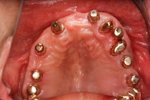

② 下あごにインプラント(人工歯根)を埋入しました。これで、まったく歯がなかったところに歯の土台が固定されました。

ここに、人工の歯を乗せしっかりと固定します。従来の入れ歯は歯がまったくない場合、歯肉に乗せるしかありませんでした。

③ 下あごの人工歯です。インプラントの上にキャップを入れてあります。